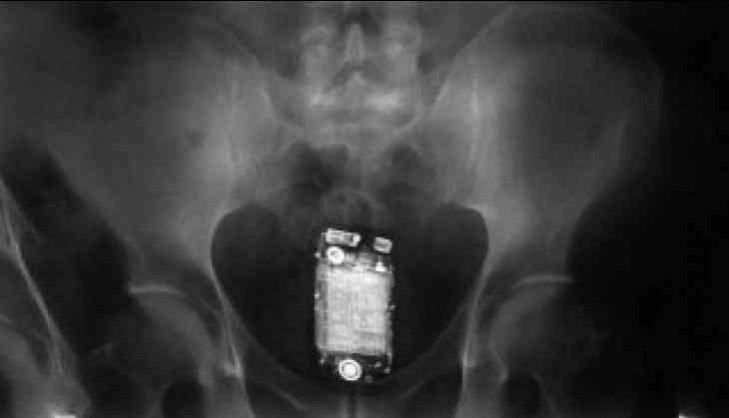

A prisoner at the high-security Tihar Jail in the national capital was hospitalised after he swallowed a mobile phone, an official said here on Friday.

"One inmate of Jail no.1, Tihar, swallowed a mobile phone when our staff approached him for search on suspicion," the DG said.

He informed that the said inmate was then immediately taken to the Deen Dayal Upadhyay Hospital in the city.

"Although his condition was fine so far, but mobile phone was still inside his body," Goel said.